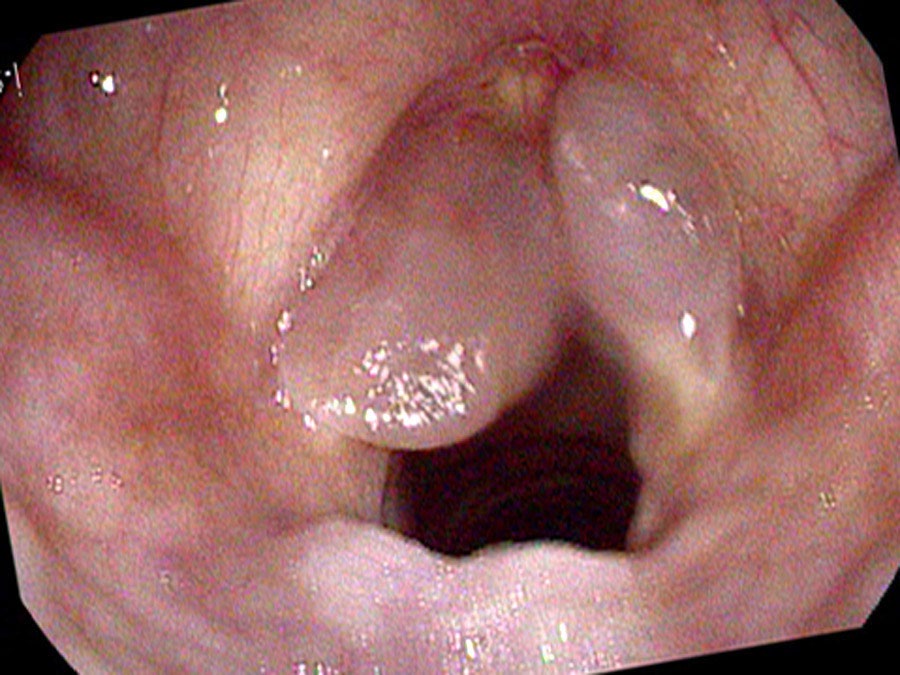

On endoscopy there are large polyps extending the length of both vocal cords, based on the superior surface and moving in and out with speaking and breathing. At times they get caught below her vocal cords and no sound comes out at all. Because they are so large, at times she squeezes her false vocal cords together and makes them vibrate. This combination produces her characteristically very deep, rough voice: up to three pitches generated simultaneously from the asymmetric true cords and the vibrating false cords.

Quitting smoking will not generally reduce the size of the polyps, though it may stabilize them. Quitting talking seems never to be an option for these patients. Consequently, treatment with surgery or laser is typically reserved for those who desire a higher speaking pitch or those whose polyps are large enough to impair breathing.